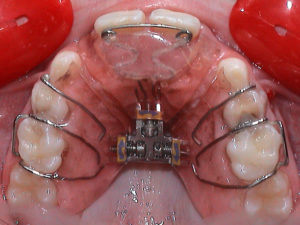

Fixed Maxillary Expansion appliances. The most common are:

- Συσκευή Hyrax

- Συσκευή Hyrax